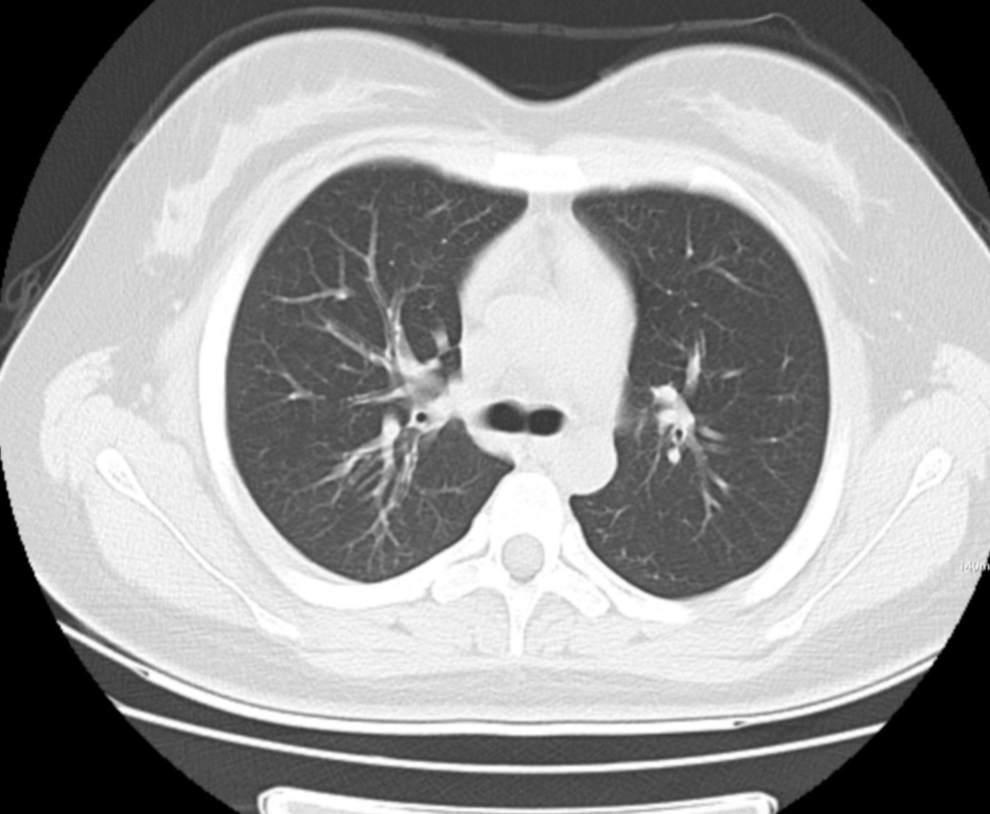

肺部CT:

支气管血管束增粗且伴 < 2 个肺叶的磨玻璃密度影, 多提示为单纯性百日咳肺炎。(下图:支气管血管束增粗, 两肺下叶基底段少许磨玻璃密度影)

如出现肺内支气管血管束增粗, 伴≥3 个肺叶斑片影、亚段性实变及支气管气象时, 提示患儿病情较重,可能合并其他感染。